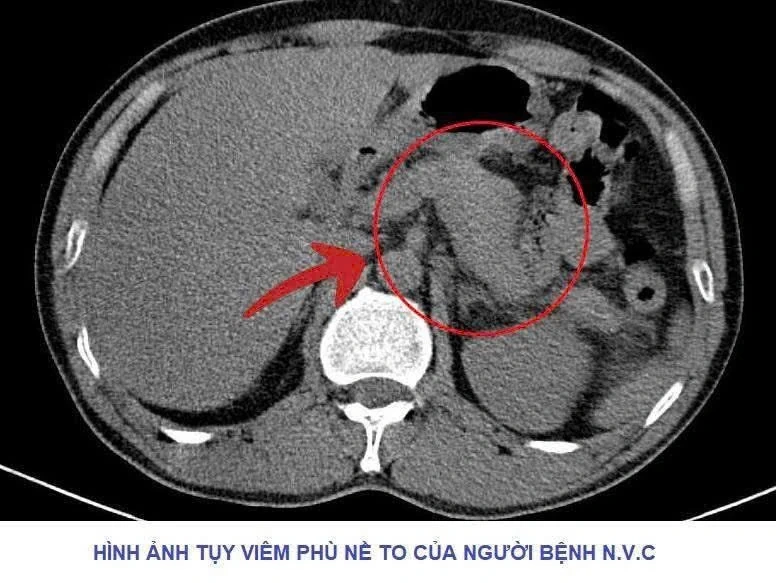

Sau khi bác sĩ tiến hành thăm khám, thực hiện các cận lâm sàng cần thiết, kết quả cho thấy tuyến tụy to, có thâm nhiễm viêm, chỉ số men Amylase vượt ngưỡng rất cao. Các bác sĩ nhanh chóng hội chẩn và xác định người bệnh mắc viêm tụy cấp, chỉ định đặt sonde dạ dày và đặt đường truyền tĩnh mạch trung tâm.